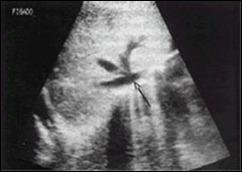

First, the doctor should do a good physical exam, get a good patient history (anamnesis) and order some tests according to need.Ultrasonography of the biliary tree is not a very good tool to see the stones within the common bile duct or the cause of obstruction, however, will show the consequences of this obstruction, which are dilated biliary ducts. This test has the advantage of being low cost.

Magnetic resonance cholangiography of the biliary tract may be ordered to locate the presence of calculus. It has the disadvantage of being expensive.